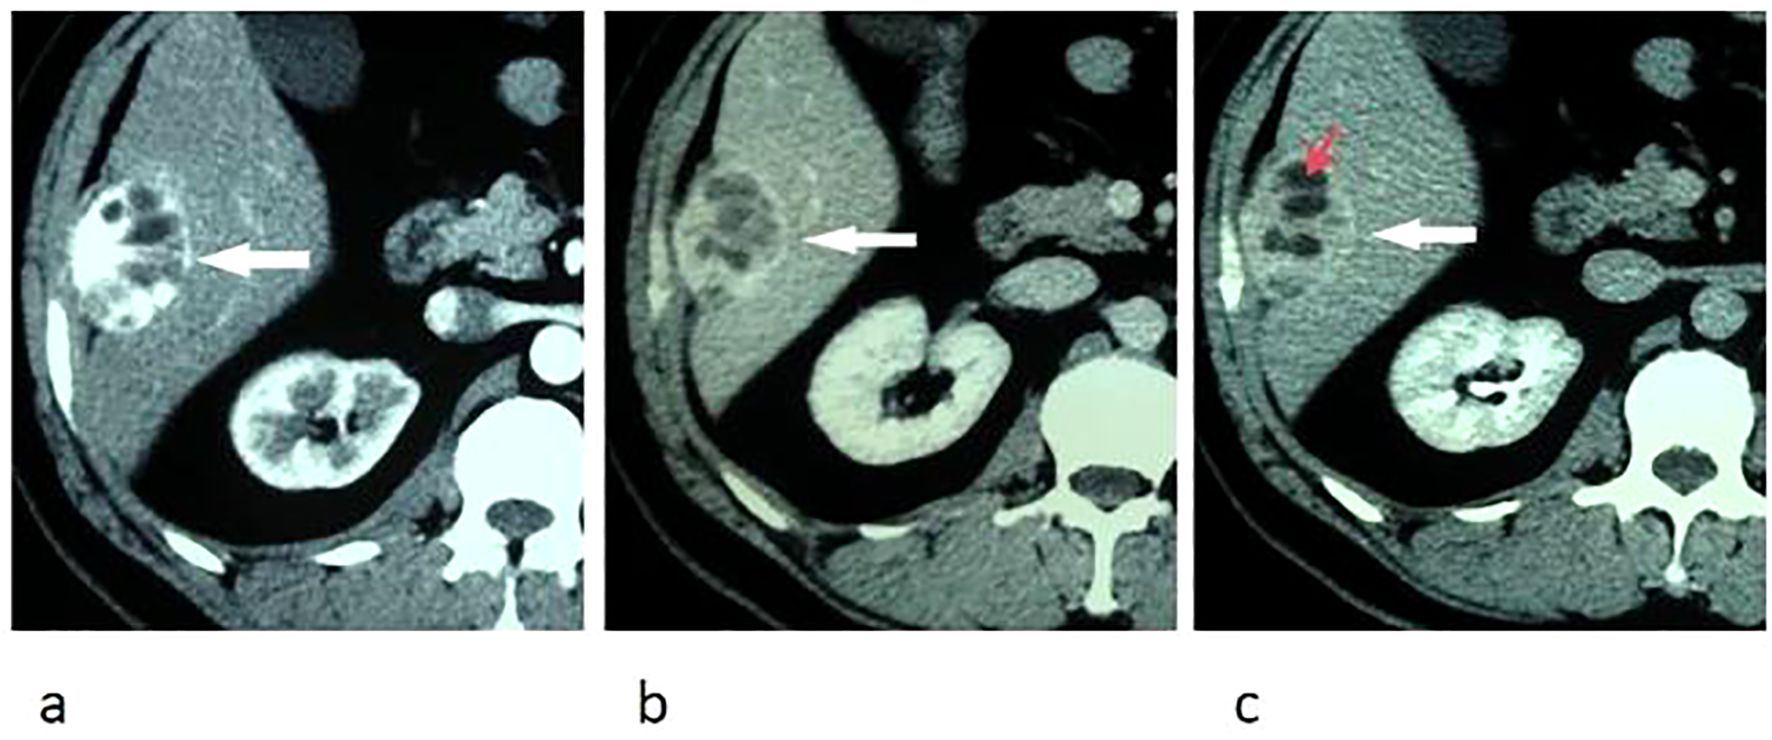

On abdominal CT images, the larger mass was heterogeneous with some intratumoral multilobulated cysts, and the smaller nodule was homogeneous, measuring 4.5 cm and 1.5 cm correspondingly, both of which were closely related to the peritoneum. The tumors were hypervascular, demonstrating marked enhancement in arterial phase and prolonged enhancement in portal venous and delayed phases after intravenous injection of contrast material (Figure 1).

Figure 1. Transverse CT images of arterial phase (a), portal venous phase (b), and delay phase (c) show marked and prolonged enhancement of an oval liver mass, with unenhanced intratumoral cystic areas (red arrow) and enhanced capsule (white arrow).